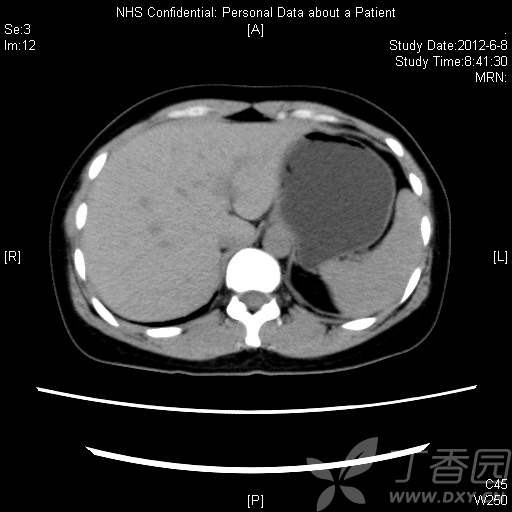

患者36岁女性,体检发现左肾实性占位,无自觉症状。

CT资料: